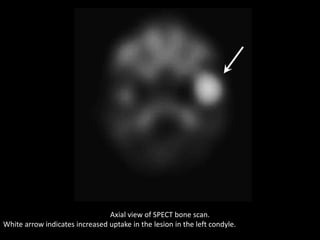

Axial view of SPECT bone scan.

White arrow indicates increased uptake in the lesion in the left condyle.